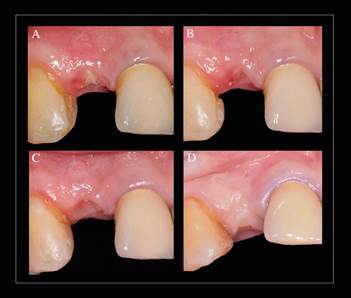

Clínicamente el alveolo post extracción se mantuvo indemne y con su arquitectura gingival conservada, excepto en apical en donde hubo una pequeña perforación de la tabla vestibular en relación a la lesión apical. Se realizó la instalación inmediata yuxtaósea de un implante Straumann Bone Level Tapered® (Basilea, Suiza) de 3.3 x 12mm, y posteriormente se rellenó el espacio entre la tabla ósea vestibular y el implante (gap) con un xenoinjerto de origen bovino (Geistlich Bio Oss®, Geistlich Pharma AG, Suiza), el cual fue cuidadosamente condensado (Figura 3). Finalmente se cerró el contorno de entrada al sitio implantario con una matriz colágena de origen porcino (Geistlich Mucograft® Seal, Geistlich Pharma AG, Suiza) de 8 mm, posicionando su capa compacta, delgada y lisa en relación al epitelio y su capa porosa no compacta en relación al sitio implantario. La matriz fue recortada de acuerdo a las medidas del alveolo, teniendo en cuenta que fuera levemente más grande, de modo que no quedara suelta dentro del alveolo, sino con una leve retención y autocontenida. Para garantizar su posición se suturó mediante un punto colchonero horizontal cruzado, utilizando Nylon 5-0 (Ethilon®, Johnson & Johnson de Chile S.A, Chile), sin perforar la matriz colágena (Figura 4). Finalmente para mantener la estética del sector anterior se instaló un provisorio adhesivo tipo Maryland.

Se evaluó clinicamente la regeneración de tejido blando a partir de la matriz de colágeno porcino colocada en el alveolo, utilizando la escala de evaluación de cicatriz de Stony Brook7. En esta escala se describen 5 categorías a evaluar: 1) Ancho, 2) Altura, 3) Color, 4) Marcas de sutura y 5) Apariencia general. Esta escala fue utilizada para la evaluación clínica durante los controles de la 1a semana, 3a semana, 5a semana y a los 6 meses, posteriores a la colocación de la matriz colágena porcina (Figura 5).

La evolución de la regeneración de tejido blando a partir de una matriz de colágeno porcino, fue paulatina y no se apreció la pérdida de la matriz injertada, con la consecuente migración progresiva del epitelio sobre ésta. Las primeras semanas se observaron en la superficie del epitelio partículas del xenoinjerto (Geistlich Bio Oss®, Geistlich Pharma AG, Suiza), las cuales fueron removidas.

Según la escala de evaluación de cicatriz de Stony Brook 7, los resultados clínicos variaron desde un puntaje de 0 para la 1a semana de control, en donde estuvo marcado por un ancho mayor a 2 mm de herida, una depresión en la zona central, un enrojecimiento de la zona quirúrgica, marcas de las suturas y una pobre apariencia estética inicial.

La 3a semana el puntaje fue de 2, marcado por un ancho menor a 2 mm de herida, una depresión en la zona central, un enrojecimiento de la zona quirúrgica, sin marcas de las suturas y una pobre apariencia estética inicial.

La 5a semana el puntaje fue de 3, marcado por un ancho menor a 2 mm de herida, una depresión en la zona central, un leve enrojecimiento de la zona quirúrgica, sin marcas de las suturas y una buena apariencia en la estética inicial.

A los 6 meses el puntaje fue de 5, marcado por un ancho menor a 2 mm de herida, sin depresión en la zona central, sin enrojecimiento de la zona quirúrgica, sin marcas de las suturas y una buena apariencia en la estética inicial.